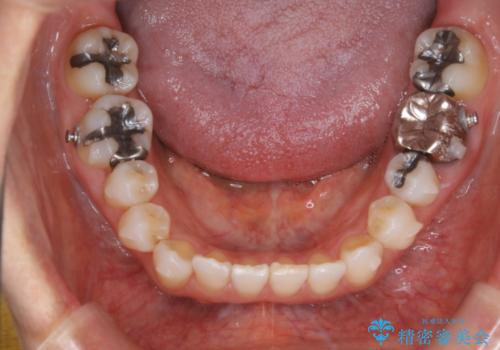

- 右上の小臼歯が二本とも90度捻じれてしまっており、奥歯の噛み合わせに問題が生じていました。

今回は右上の奥歯に入っていた銀歯の形が悪く、そのせいで歯を並べるスペースが足りない状態でした。

右上の歯の被せ物を作りなおし、適切な歯の大きさに代えてあげることによってスペースを作りました。

また、それだけではスペースが足りない為右上の奥歯は遠心移動を行っています。